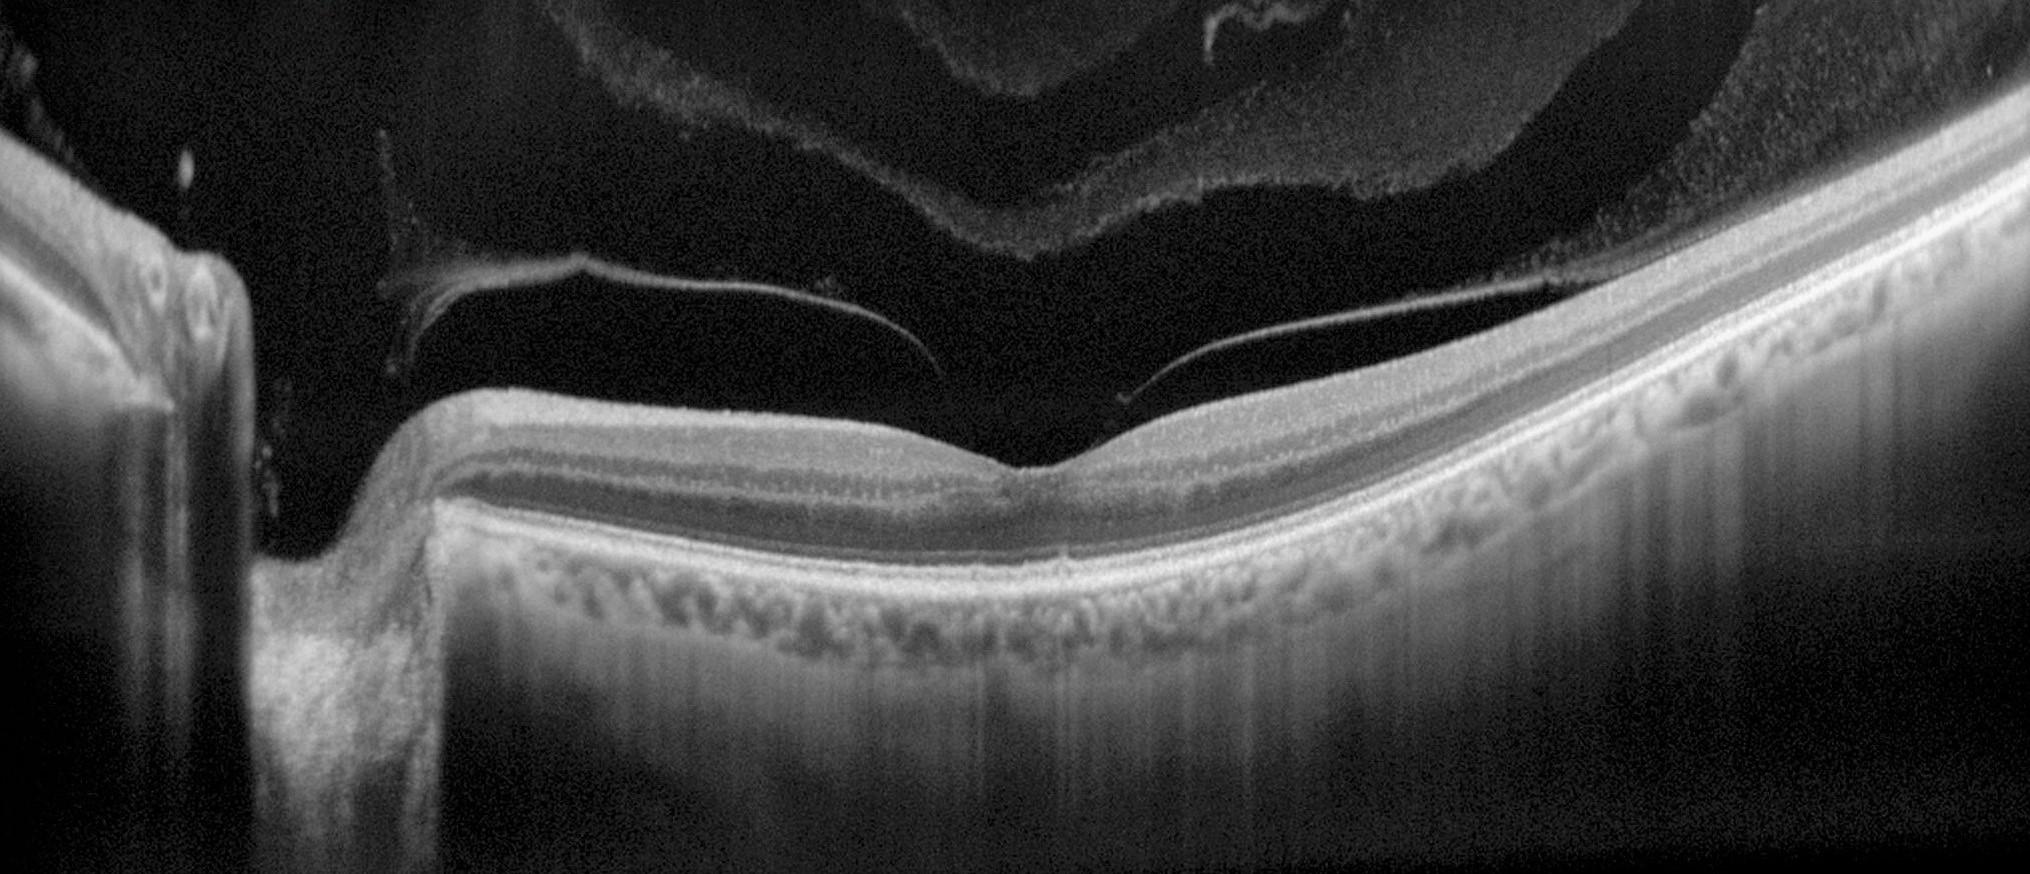

L’OCT (Optical Coherence Tomography) ou tomographie à cohérence optique, est devenu un examen indispensable pour l’analyse de la rétine. Grâce à sa méthode d’acquisition non invasive, en temps réel et d’une résolution de l’ordre du micromètre, il intervient au niveau du dépistage, de la recherche approfondie du diagnostic et du suivi patient.

Cet appareil qui balaye le fond d’œil à l’aide d’un faisceau laser reconstruit des coupes et des volumes permettant une analyse détaillée de toutes les couches de la rétine et de la choroïde. C’est donc un outil précieux de détection et de suivi des pathologies rétino-choroïdiennes et de la papille telles que la DMLA, les rétinopathies et maculopathies, les glaucomes ou encore les pathologies génétiques.

Grâce à un adaptateur ramenant le plan focal de l’appareil en avant de l’œil, ou grâce à un OCT spécifique de segment antérieur, il est également possible d’obtenir des coupes de la partie antérieure de l’œil, de la cornée au cristallin. Cette utilisation apporte des informations sur la structure de la cornée et sur l’ouverture de l’angle irido-cornéen, valeur particulièrement surveillée chez les patients atteints de glaucome. Toujours accompagnés d’un système d’imagerie du fond d’œil, les OCT sont également utilisés pour observer le réseau vasculaire de la rétine grâce à l’OCT-angiographie.

L’OCT fonctionne grâce au déplacement bidimensionnel d’une source laser infra-rouge qui balaye le fond d’œil. Comme pour l’échographie, les capteurs de l’OCT détectent les échos du signal réfléchis par les différences de composition des couches cellulaires de la rétine.

Cette technique, basée initialement sur le principe d’interférométrie présente toutes les couches cellulaires avec une résolution micrométrique. Le balayage OCT est positionné et replacé sur la rétine grâce à un autre système d’imagerie du fond d’œil, infrarouge ou SLO, qui conditionne la qualité du suivi (tracking) de la rétine pour le positionnement correct des acquisitions et les examens de suivi (coupes acquises dans les mêmes conditions).

Avec cette précision, l’ophtalmologue peut détecter dans ces images mêmes les plus fines lésions pathologiques de la rétine et de la choroïde. Par association des coupes en 2 dimensions, l’OCT permet également la reconstruction des volumes 3D du fond d’œil, acquisition indispensable pour l’étude des épaisseurs de la rétine (œdèmes et décollements de rétine) et notamment celle du complexe des cellules ganglionnaires, atteinte dans le glaucome. Ces valeurs sont comparées dans le suivi patient afin de surveiller l’évolution de la maladie, l’efficacité du traitement et d’ajuster la stratégie thérapeutique.

En segment antérieur, une lentille additionnelle avance le plan focal de l’appareil au niveau du segment antérieur, permettant ainsi une analyse en coupe de la cornée et de l’angle irido-cornéen (pachymétrie, maladies de cornée et glaucomes par fermeture de l’angle).

Qu’il soit destiné à l’analyse du segment postérieur ou du segment antérieur, l’OCT présente les couches de tissus avec une grande résolution, permettant ainsi une analyse structurelle fine des zones imagées.

OCT de segment postérieur

Avec une mise au point en profondeur, l’OCT du segment postérieur image le fond d’œil, du vitré à la choroïde. Toutes les lésions des pathologies rétiniennes et choroïdiennes peuvent ainsi être détectées pour le dépistage, le diagnostic et le suivi patient.

OCT de segment antérieur

Les OCT de segment postérieur possèdent une lentille adaptative ramenant le plan focal au niveau de l’analyse en coupe de la partie antérieure de l’oeil. Pour une meilleure pénétration, les OCT dédiés au segment antérieur ont été développés. Ils utilisent une technologie swept-source, plus adaptée à l’imagerie de la chambre antérieure et permettent une analyse détaillée de ses structures.

Les pathologies cornéennes, les anomalies cristalliniennes, le positionnement d’implant, les ouvertures de l’angle irido-cornéen… sont ainsi étudiées et suivies.